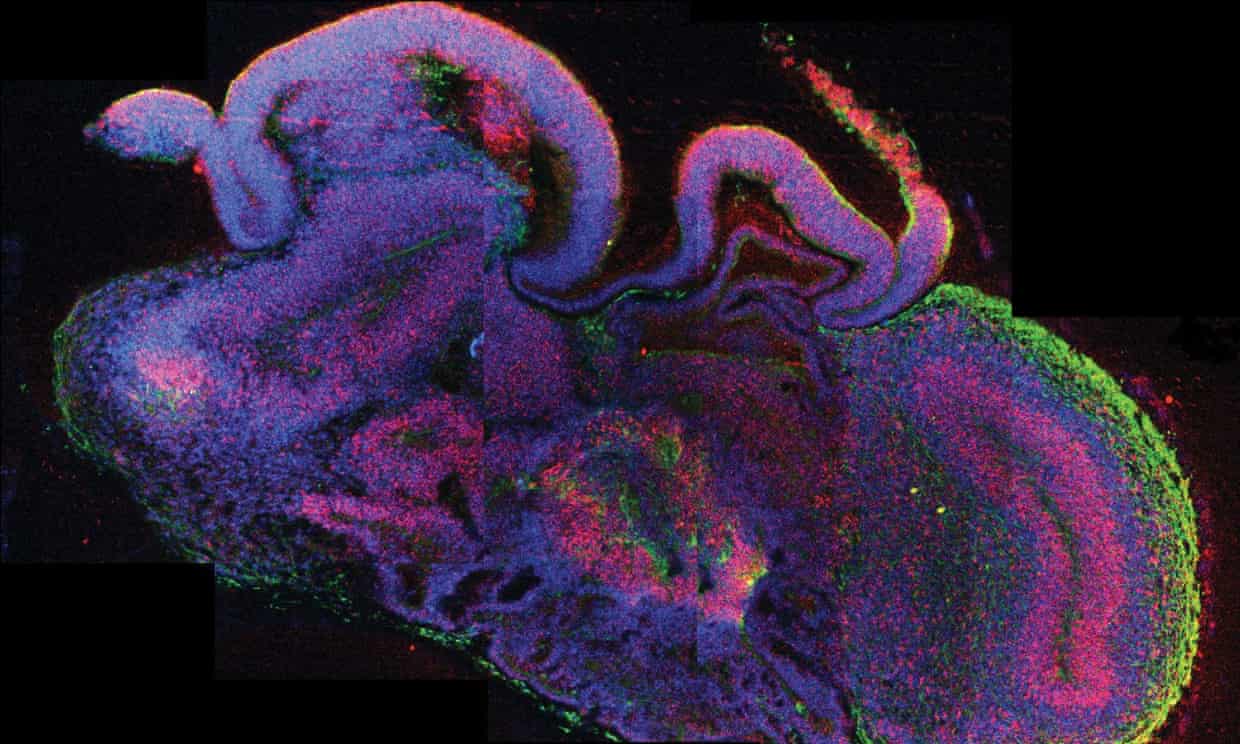

‘organoid’ Published 23/10/2019 at 1240 × 744 in Νευροεπιστήμονες ξεπέρασαν τα όρια της βιοηθικής (;) Μια τομή ενός εγκεφαλικού οργανοειδούς ‹ Back